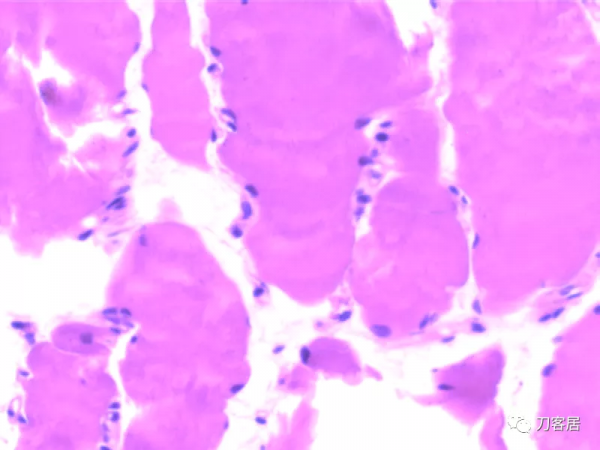

患者發病後右腿腓腸肌病理切片所見:灰紅色至綠豆大組織四塊。光鏡檢查結果:病理診斷“右側腓腸肌”肌纖維肥大變性,個別肌纖維可見溶解及空泡。患者家屬拒絕屍檢。

(6)病理學檢查右側腓腸肌肌纖維粗細不均,肌細胞漿溶解,縱橫紋不清晰,有纖維肥大變性,個別肌纖維可見溶解及空泡。根據以上特點,此患者可診斷MH。

患者發病後(右腿腓腸肌)